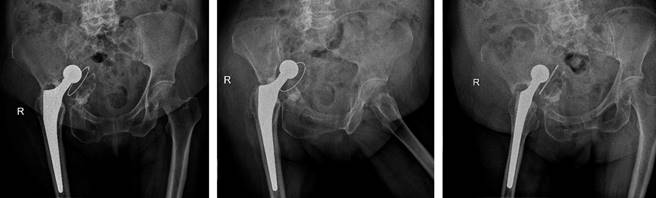

Se realiza seguimiento clínico y radiográfico a los 30, 60 días y al año, evidenciándose un Harris Hip Score final de 80 puntos y EVA de 0/10. No se evidencia migración medial de componente acetabular, además de adecuada osteointegración de los componentes protésicos (Figura 7).

Figura 7: A) Control radiográfico postquirúrgico a los 30 días. B) Control radiográfico postquirúrgico a los 60 días. C) Control radiográfico postquirúrgico al año.

Entre las técnicas, las copas y aumentos de metal altamente poroso mostraron resultados satisfactorios para corregir defectos severos como es el caso expuesto con una mejoría en HHS de 64 puntos y EVA de 8 puntos al año postquirúrgico.